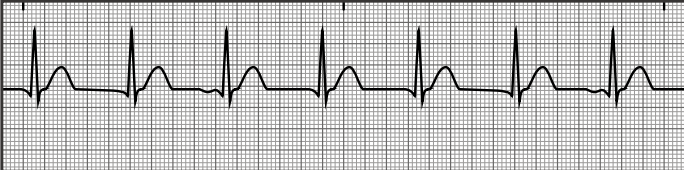

premature junctional complex

junctional escape rhythm

accelerated junctional rhythm

bundle branch block

pacemaker spikes